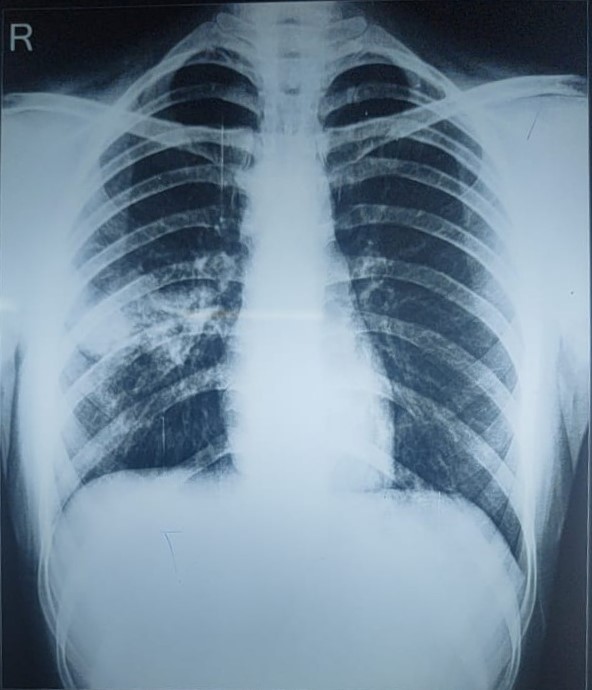

| 127 | IGGMC, Nagpur, Nagpur | P2 | 29-4345 | Hiraman Tembhurne | Consent taken on Paper | 62 Yrs. |

Provisional Diag : Dyspnea

Final Diag : Post TB With Interstitial Lung Disease |

Post TB Sequelae | Bilateral Cystic Opacity Upper, Mid & Lower Zone/ Bilateral Reticular Opacites/ Bilateral Fibrotic Bands Present/ Decrease Lung Volume/ Few Old Calcific Nodules | Abnormality visible on x-ray |